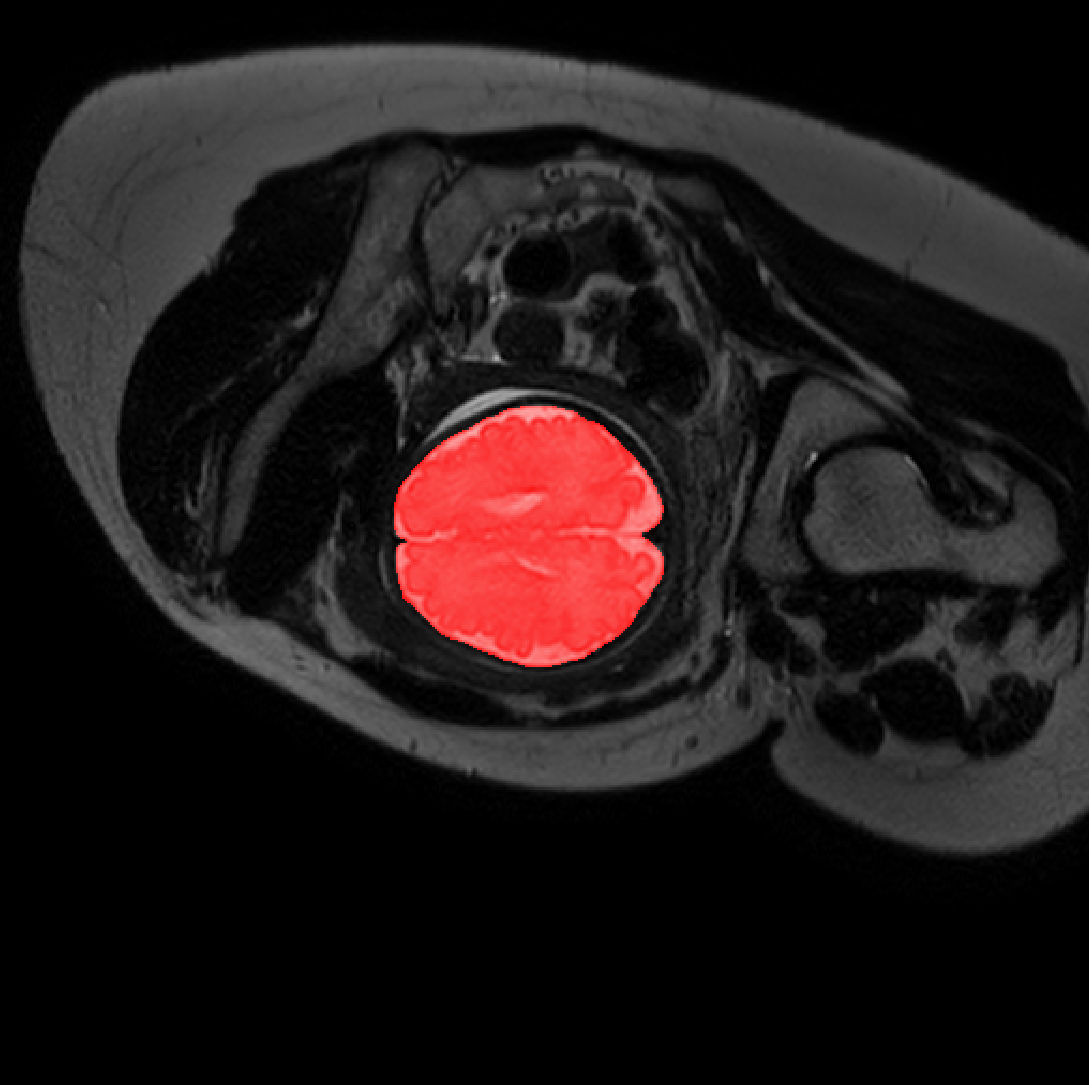

Table 1 lists average of quantitative evaluation results of these experiments and Figure 2 shows results obtained from each image. Figure 3 shows examples of the obtained segmentations.

Refer to caption

Figure 3: Example of ICV segmentations in images acquired in axial (left), coronal (middle) and sagittal (right) planes. Top row: A slice from T2-weigted image; Second row: Automatic segmentations obtained using 7 training images from the representative imaging planes; Third row: Automatic segmentations obtained using all 21 training images from all 3 image orientations; Bottom row: Manual segmentation.